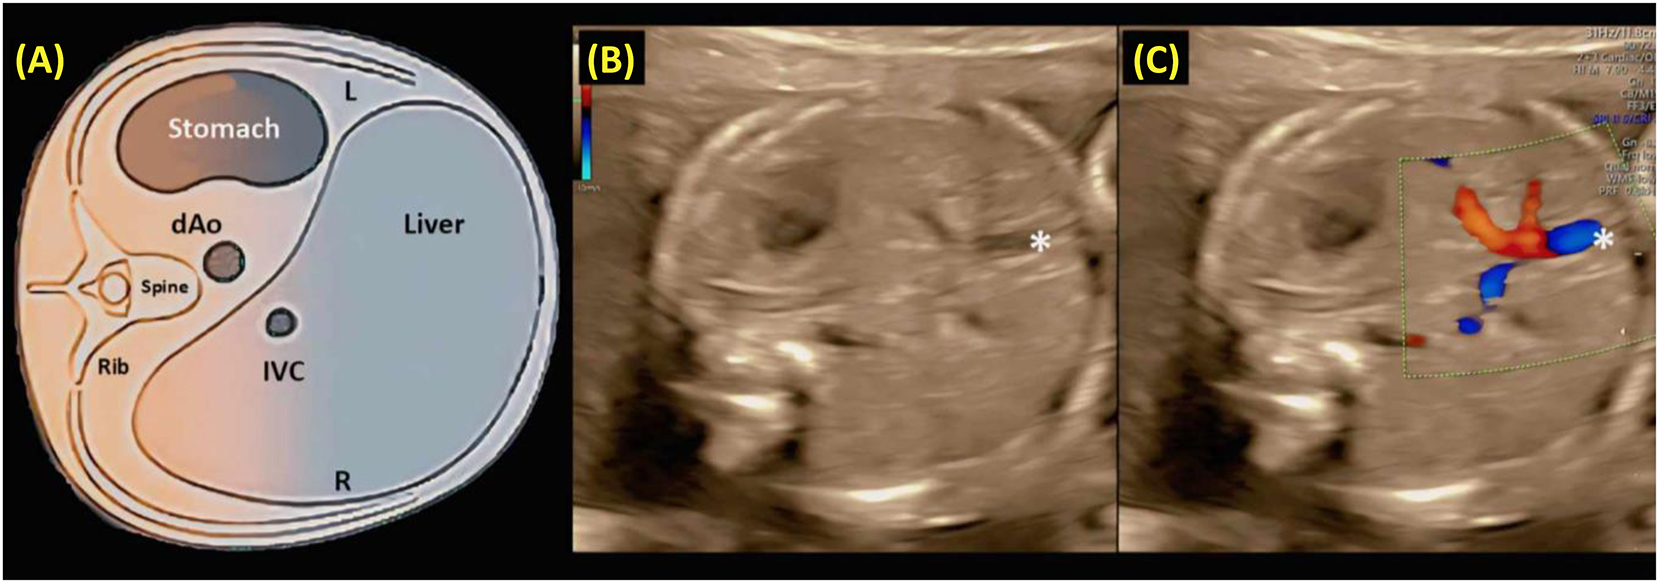

Evaluating fetal situs involves identifying the right and left sides to establish normal abdominal and cardiac orientation; transverse ultrasound sweeps confirm that both the stomach and heart are correctly positioned. Abdominal situs verification checks that the stomach, descending aorta, and inferior vena cava align properly relative to the spine, typically correlating with atrial situs solitus. In the four-chamber view, the heart should occupy about one-third of the chest cavity with a long-axis orientation of roughly 45° (±20°); structural deviations may indicate underlying CHDs, necessitating further imaging [3], 4], 9], 11], 24]. Figures 9–11, respectively, illustrate the assessment of fetal abdominal situs using grayscale and Doppler ultrasound, evaluation of fetal cardiac position and axis, and key components of the four-chamber view essential for detecting CHDs [9], 11], 16], 18], 23], 24]. One such structural anomaly is an atrial septal defect (ASD), which may be suspected in the four-chamber view and confirmed through advanced modalities such as STIC 4D ultrasound. Figure 12 illustrates a clear case of ASD, showing a persistent opening in the atrial septum that enables abnormal blood flow between the left and right atria. This dynamic imaging provides precise anatomical detail – including the size and location of the defect – and plays a crucial role in prenatal diagnosis, perinatal risk assessment, and postnatal management planning (Figure 13).

A schematic diagram (a), along with grayscale (b) and color Doppler (c) ultrasound images, depicting an axial view of the fetal upper abdomen. (A) The transverse view of the fetal abdomen is used to assess abdominal situs. After establishing fetal laterality based on the position in utero, the stomach should be observed on the left side of the fetus, while the descending aorta (dAo) and inferior vena cava (IVC) are located to the left and right of the spine, respectively. (B, C) A short segment of the umbilical vein (*) is visible in the center of the liver. L and R indicate left and right [3], [4], [5, 9], 11], 17], 24], 65], 66].](/document/doi/10.1515/jpm-2025-0037/asset/graphic/j_jpm-2025-0037_fig_009.jpg)

A schematic diagram (a), along with grayscale (b) and color Doppler (c) ultrasound images, depicting an axial view of the fetal upper abdomen. (A) The transverse view of the fetal abdomen is used to assess abdominal situs. After establishing fetal laterality based on the position in utero, the stomach should be observed on the left side of the fetus, while the descending aorta (dAo) and inferior vena cava (IVC) are located to the left and right of the spine, respectively. (B, C) A short segment of the umbilical vein (*) is visible in the center of the liver. L and R indicate left and right [3], [4], [5, 9], 11], 17], 24], 65], 66].